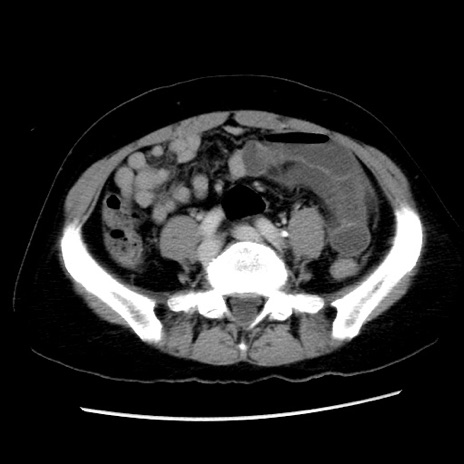

冠状断像

【症例】 50歳代女性

【主訴】 腹痛

【現病歴】前日生レバーを食べた。今朝に排便あり。 昼前に突然発症の腹痛を生じ、当院救急外来を受診した。

【既往歴】 子宮筋腫にてで子宮全摘後

【身体所見】 意識清明、腹部:平坦、軟、下腹部やや左を中心に圧痛・反跳痛あり、筋性防御あり

【データ】WBC 7800、CRP 0.07